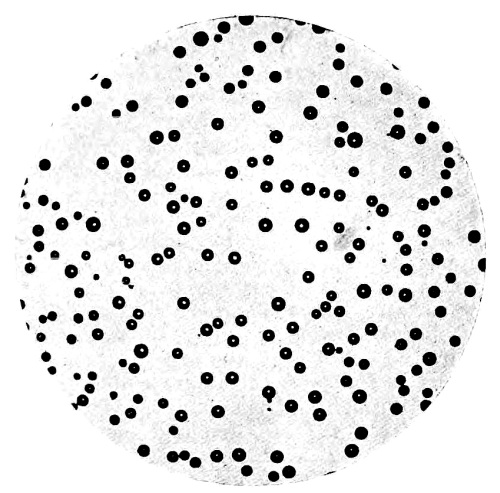

35. Photo-micrograph of Globules of Mercury obtained by Reinsch‘s Process 303